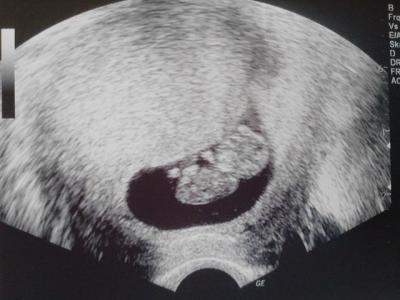

Hallöle. Bisher saß ich im Februar-Mami-Bus und muss nun eigentlich umsteigen denn bei meinem heutigen FA Besuch wurde mein ET auf den 29. Januar vorverlegt. Würd mich freuen mich nun bei euch einreihen und mit euch zusammen auf das große Ereignis hinfiebern zu dürfen. LG Mugelchen (mein Nickname kommt übrigens von meinem Freund. Als ich meinte das ich jetzt stetig dicker werd und bald ne Kugel mit mir rumschiebe, sagte er das ich zur Mugel werd ... halb Mensch halb Kugel) Anbei übrigens ein Bildchen unsres Gummibärchens.

Unsre Größe liegt aktuell bei 3,2 cm. Meinen nächsten Termin hab ich erst in 6 Wochen da meine FA bald drei Wochen Urlaub macht und ich so entweder in zwei Wochen wieder hin könnte oder eben in 6 Wochen. Ich hab mich für die 6 Wochen entschieden weil sie dann wieder US macht und man evtl schon sieht was es wird. Mein gummibärchen hat sich heut scho gut bewegt und das Herzchen hat super geschlagen. Muss sagen das dieser Zwerg nicht geplant war weil ich momentan durch ne stressige Zeit geh und ja schon drei Kids hab. Aber die Pille wollt net so recht funktionieren und nu isses eben so. Abtreibung geht mal gar nicht und deswegen wars keine Frage das Krümelchen zu bekommen. Wo Anfangs noch arge Bedenken waren macht sich nun umso mehr Freude breit.